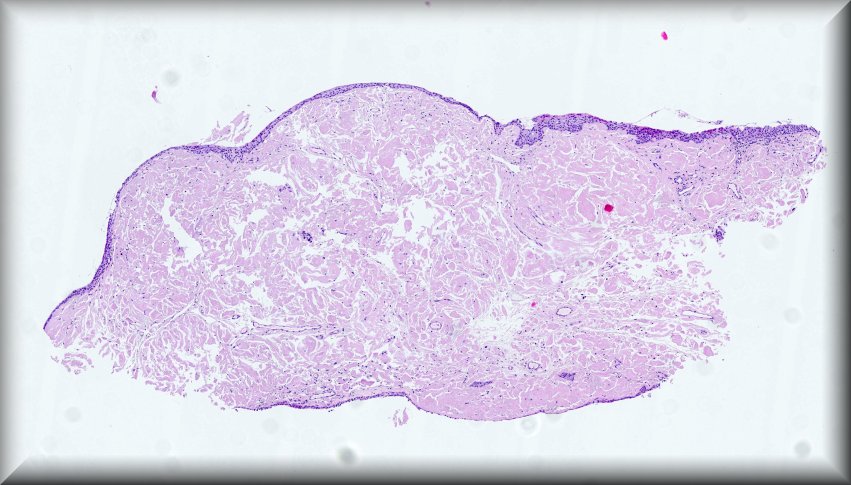

Steffen Heegaard (Copenhagen): Haemolacria in a 72-year-old man. Protocol |